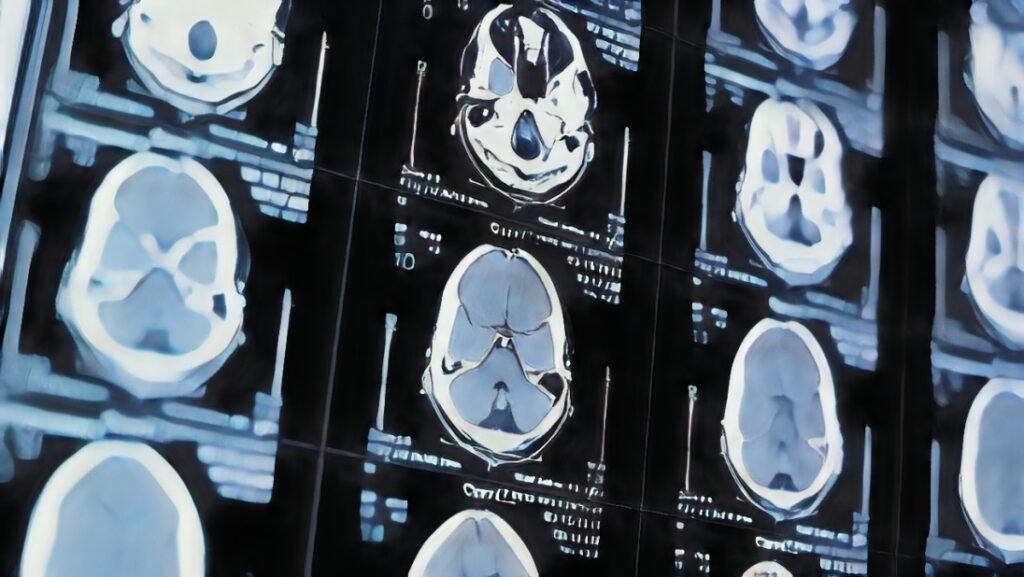

Un estudio pionero, publicado en la revista Nature Communications y liderado por investigadores de la Universidad de California en Irvine, ha revelado que las alteraciones en la forma del cerebro podrían ser un indicador temprano del desarrollo de demencia, incluso antes de que se manifiesten los primeros síntomas clínicos. El equipo analizó más de 2,600 imágenes cerebrales de individuos entre 30 y 97 años, identificando patrones de cambio en la geometría cerebral que están asociados con el deterioro cognitivo y podrían anticipar la aparición de enfermedades como el Alzheimer.

Los resultados mostraron que, a medida que las personas envejecen, algunas regiones del cerebro se expanden, mientras que otras se contraen. En particular, las áreas inferiores y frontales tendían a aumentar de volumen, mientras que las regiones superiores y posteriores experimentaban una reducción. Estos cambios eran más evidentes en adultos mayores con problemas de memoria, razonamiento y otras funciones cognitivas, lo que sugiere que podrían servir como un marcador temprano para detectar el riesgo de demencia.